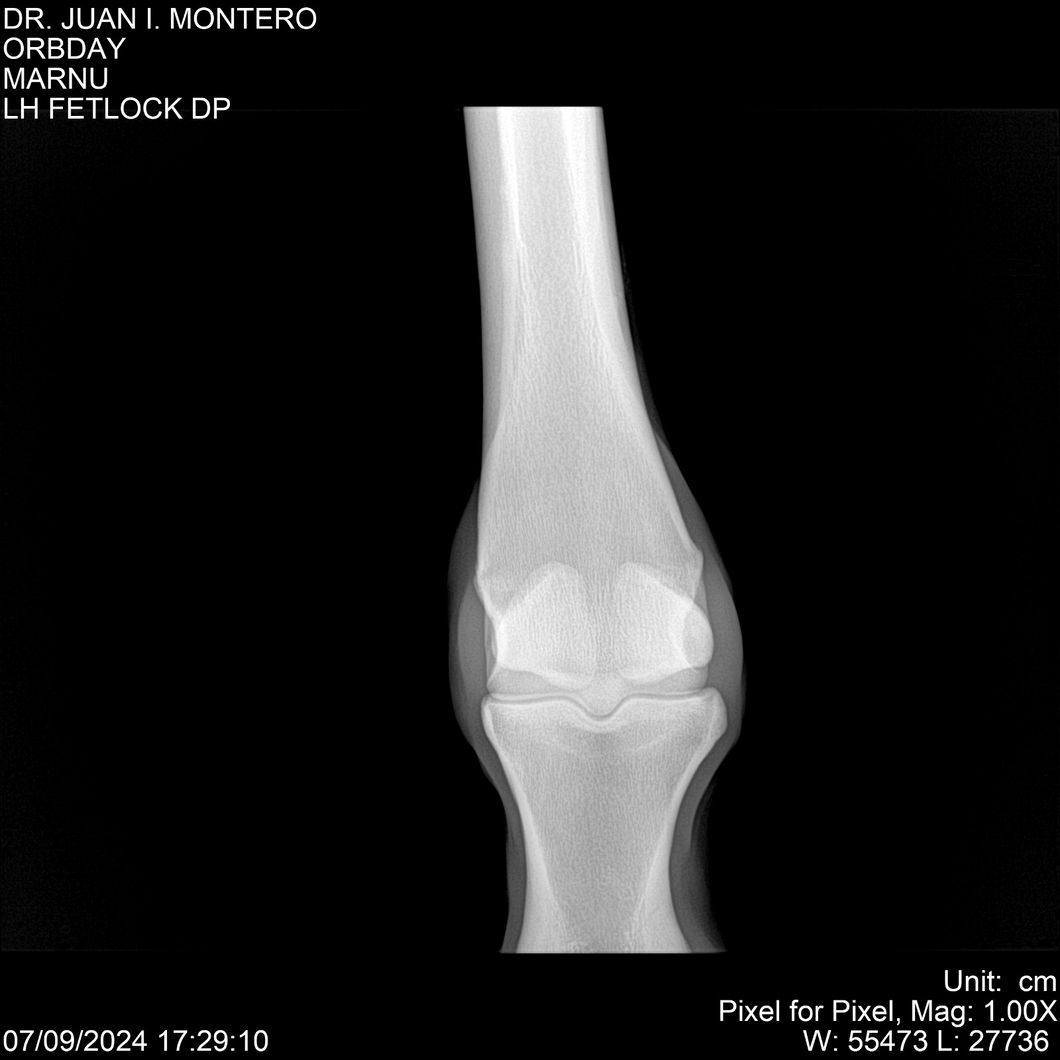

• Empresa: Abelenda N. R., Walter Hugo